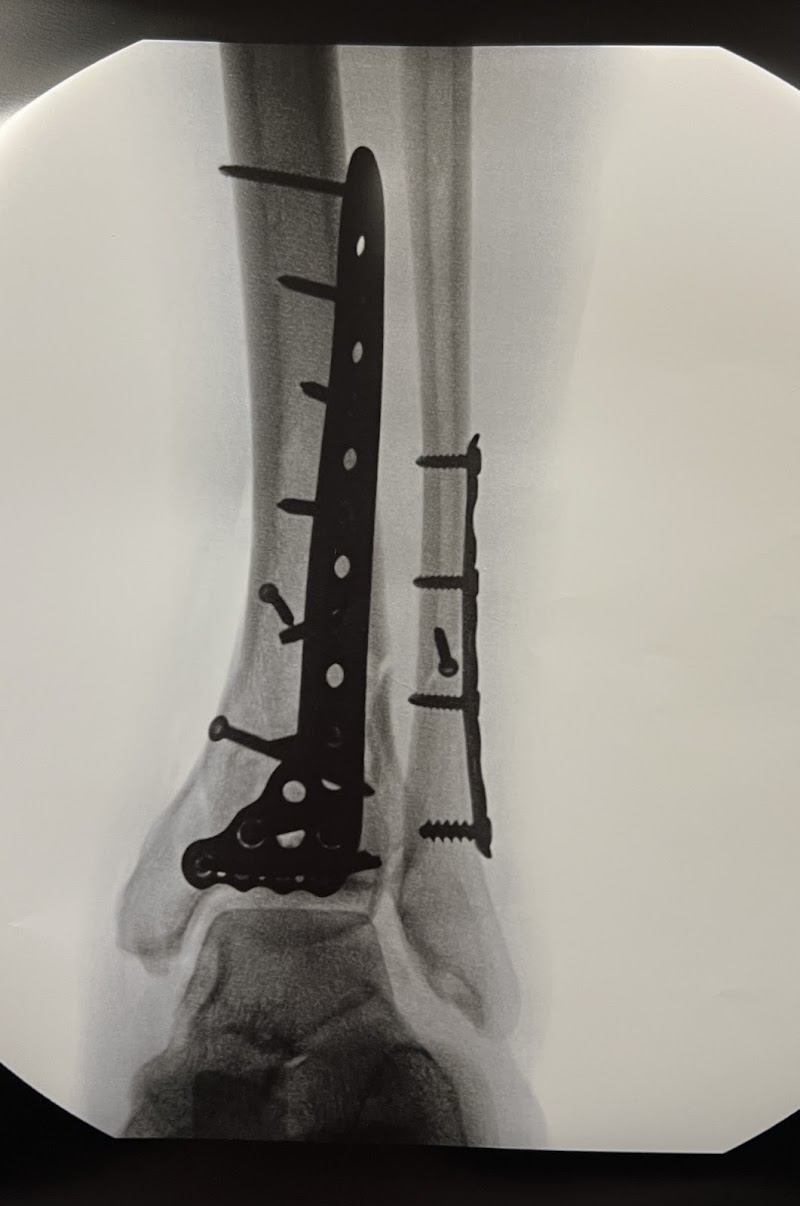

Our orthopedic team treats conditions affecting the bones, joints, muscles, and connective tissue. Common presentations include knee and hip pain, rotator cuff injuries, back and neck problems, sports injuries, and osteoarthritis.

Orthopedic surgeons diagnose and treat musculoskeletal conditions medically and surgically. Physical therapists provide rehabilitation and exercise-based treatment. Both disciplines often work together, with PT frequently used before or after surgical intervention.

Most orthopedic conditions are initially managed conservatively with physical therapy, injections, or medication. Surgery is typically considered only after conservative approaches have been tried adequately and symptoms persist or functional limitations remain significant.